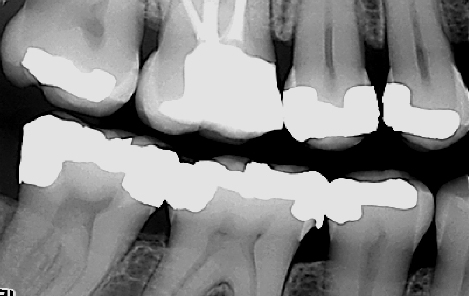

Tannlegen må også vurdere behovet for å ta røntgenbilder i forbindelse med undersøkelsen. Røntgenbilder brukes for å diagnostisere sykdommer i de deler av tennene som ikke er synlige i munnen. I tillegg kan de avdekke patologi i kjevene. Eksempler på slike sykdommer kan være hull under gamle fyllinger eller kjevecyster. I tillegg kan tannlegen sammenligne røntgenbilder tatt over flere år. Slik kan tannlegen vurdere hvorvidt en tilstand (for eksempel et begynnende hull) har utviklet seg eller ikke.

Det finnes ulike former for røntgenbilder. Ved en regelmessig undersøkelse er det vanligvis bitewings som benyttes. Bitewings gir tannlegen informasjon om blant annet hull i tennene, begynnende hull og kvaliteten til gamle fyllinger. De kan også si noe om tennenes feste og avdekke tegn til periodontitt (tannløsningssykdom). Ved behov kan bitewing-bildene suppleres med andre småbilder (for eksempel rotbilder) av avgrensede områder.